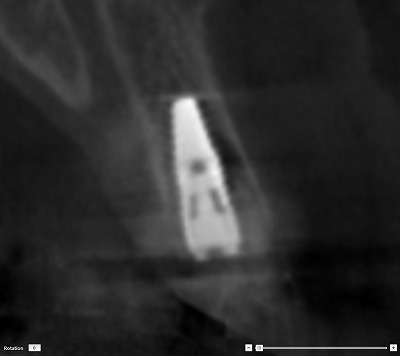

手術する前にCTレントゲンを撮ることで、インプラントを埋入する部位の骨の厚みや形を診断します。安全かつ適切な手術を行うためには、必要必須の検査です。これは、術前のCTレントゲンによる断層写真です。インプラントを描画してシュミレーションします。

手術した後のCT画像です。シミュレーション通り、正確な位置にインプラントが入っています。インプラント埋入費用と抜歯即時費用、それとセラミッククラウンの被せ物を併せて、総額432,000円(税込)になります。